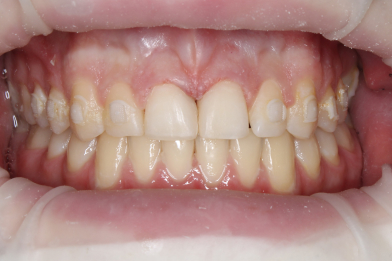

«Реставрация 1.1,2.1 зуба после ортодонтического лечения» доктора: врач - ортодонт Таранова К.С. ; врач- терапевт Рахманова М.А.

Рахманова Марина Александровна -